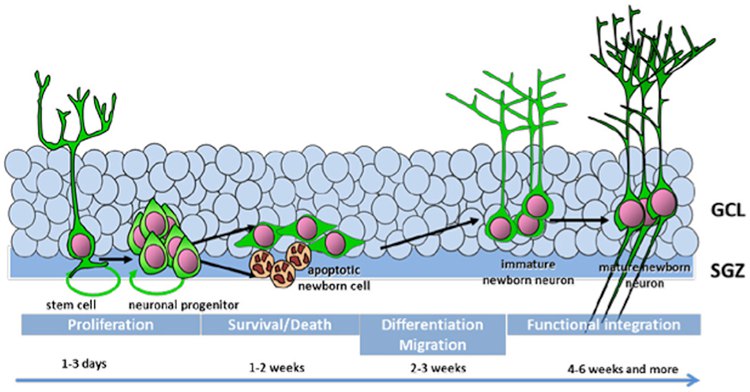

Образование новых нейронов (нейрогенез) происходит в ограниченном количестве, особенно в областях гиппокампа, который играет ключевую роль в процессах памяти и обучения. На функциональном уровне это может проявляться в изменениях когнитивных функций, таких как память, способность к обучению и скорость обработки информации.

Выращивание дополнительной мозговой ткани должно производиться на открытом мозге человека (находящегося в искусственной коме) с участием его стволовых клеток, при их некоторой контролируемой стимуляции к росту (дело это очень непростое, но принципиально осуществимое). То есть, по сути, мы должны на имеющемся старом, но ещё живом и нормально функционирующем мозге вырастить его немного уменьшенную копию.

В рамках вышеописанной процедуры переноса личности потребуется вырастить дополнительно не менее 20 миллиардов нейронов. Но при современных технологиях за месяц можно вырастить их лишь несколько миллионов. Конечно, это слишком медленно и практика выращивания нейронов постоянно совершенствуется.

В настоящее время индуцированные плюрипотентные стволовые клетки (iPSCs) для генерации нейронов получают путем “перепрограммирования” соматических клеток взрослого организма, что позволяет создавать нейроны, идентичные тем, что находятся в мозге. Через специфические культуральные и химические условия (дифференциацию) можно получать нейроны, специализирующиеся на различных функциях мозга.